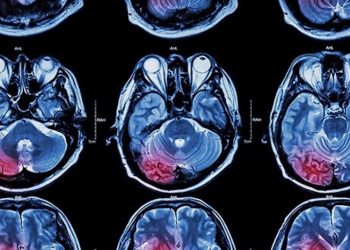

CBD zur Behandlung von Hirntumoren

Kürzlich wurden neue Studienergebnisse veröffentlicht, die in einem Forschungsprojekt der St. George's University of London in Zusammenarbeit mit der Dove ...